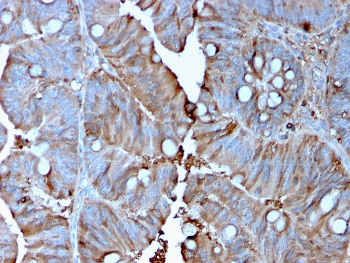

IHC staining of FFPE human colon carcinoma with MerTK antibody (clone TPKR-1). HIER: boil tissue sections in pH9 10mM Tris with 1mM EDTA for 10-20 min and allow to cool before testing.